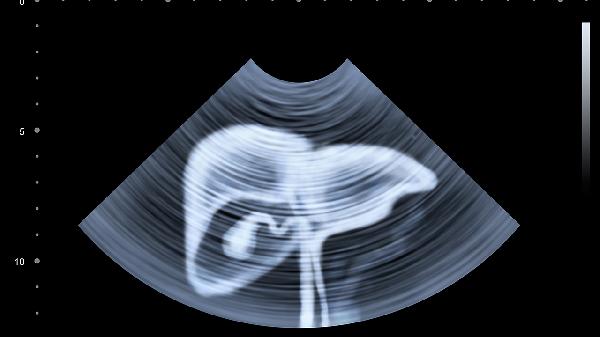

确诊肝脏低回声结节需要通过多种检查手段。影像学检查如超声、CT或MRI可观察结节的大小、形态和位置。血液检测包括肝功能、肿瘤标志物如AFP和病毒性肝炎筛查,有助于判断病因。对于可疑病例,病理活检是确诊的金标准。